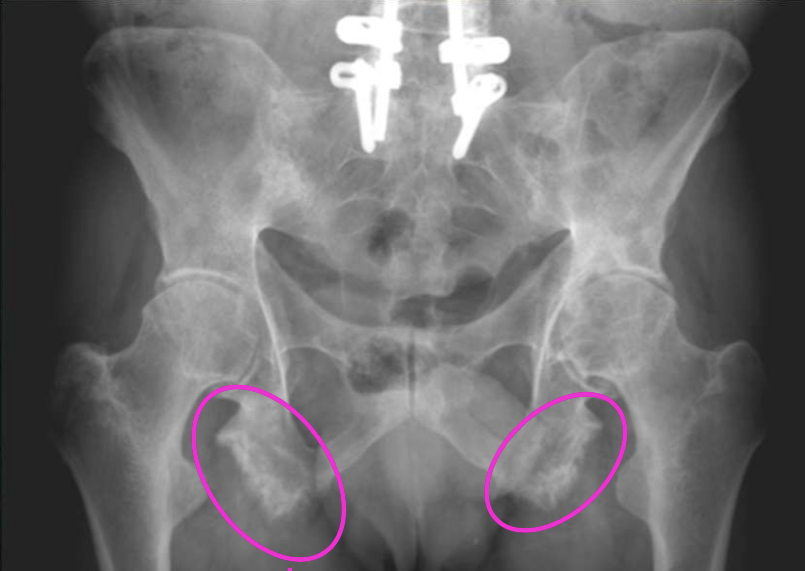

What finding of AS is found in this image

Ischial enthesopathy (Whiskering)

Ischial enthesopathy (Whiskering) could be found in AH as well, how would you ddx

via SI joints